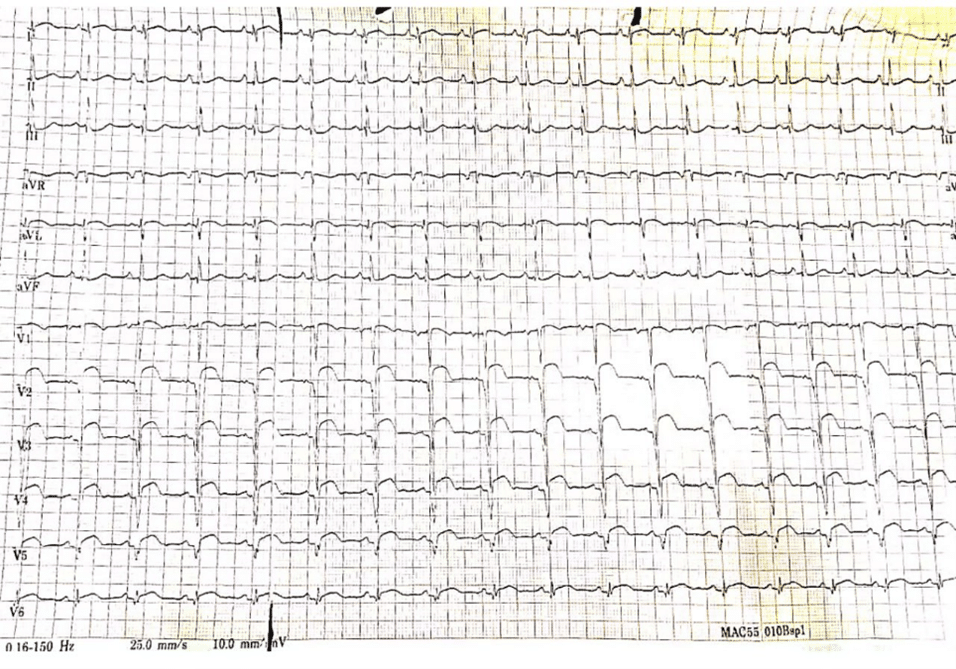

His physical examination yielded unremarkable findings. ECG displayed a normal sinus rhythm with ST-segment elevation in the anteroseptal and anterolateral leads. The echocardiography report revealed a dilated left atrium and reduced global systolic function of the left ventricle with an estimated ejection fraction of 30-35%. There was akinesis noted in the basal and mid anterior, anterolateral, and anteroseptal walls, as well as in the apico-anterior and lateral walls. The right ventricular systolic function was preserved with a tricuspid annular plane systolic excursion (TAPSE) of 24mm. No intracardiac thrombus, mass, or vegetation was observed, and both the intra-atrial and intraventricular septa appeared intact.

Figure 1: ECG displayed a normal sinus rhythm with ST-segment elevation in the anterio-septal leads and anterio-lateral leads

Symptoms of KD include fever, rash, oral mucositis, conjunctivitis, lymphadenopathy, and skin peeling. Common laboratory findings include leukocytosis, thrombocytosis, elevated ESR, positive C-reactive protein (CRP), and slightly elevated serum transaminase levels. Our patient has an elevated ESR, elevations in serum transaminases, and raised troponin. Antinuclear antibodies and rheumatoid factors are typically absent. Mild to moderate increases in serum transaminases or gamma-glutamyl transpeptidase occur in 40% to 60% of patients, with mild hyperbilirubinemia in about 10% of cases [23]. Hypoalbuminemia is common and linked to more severe and prolonged acute disease [24]. The primary complication of KD is the development of coronary artery aneurysms (CAAs), which can lead to myocardial ischemia, myocardial infarction, and sudden death. These aneurysms can cause thrombosis and progressive stenosis, potentially leading to late ischemic heart disease [25]. KD that goes undiagnosed in childhood can present as myocardial infarction in adulthood. Our patient presented with acute myocardial infarction with ST-segment elevation in the anteroseptal leads and anterolateral leads.